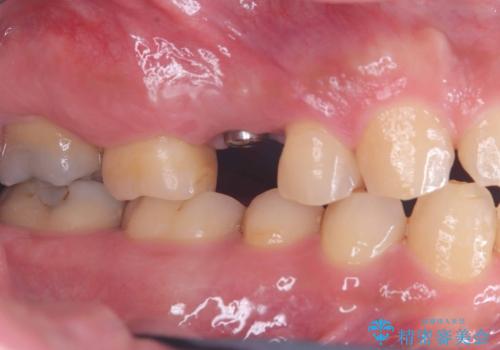

右上5番が根尖性歯周炎と歯周病が同時に併発しており、骨が大きく溶け、歯の動揺も著しかったため保存困難と判断をし抜歯してインプラントで治療を行いました。

インプラントはインプラント周囲炎になりにくいスクリュータイプを使用しています。

右上4番は虫歯になっていたので、虫歯を除去後、セラッミクインレーで治療を行いました。

従来のインプラント治療では、オペを二回に分けることが主流でしたが今は1回のオペで治療を終える事が出来るようになりました。

オペの回数を最小にする事で患者様の治療への負担が減り、治療期間も従来の治療より大幅に短くする事が可能です。